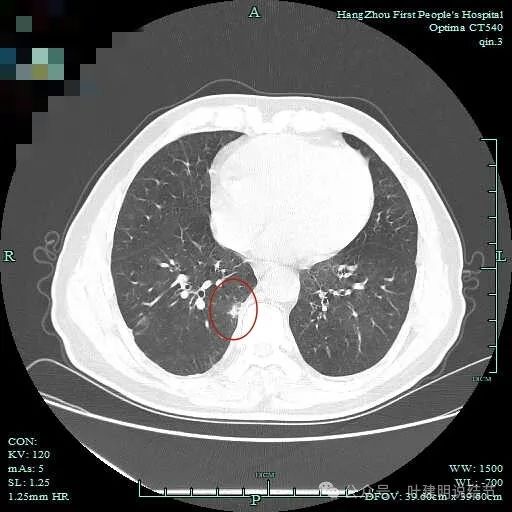

有细小血管进入,但说不上异常增粗。病灶仍是小片状,条状。

磨玻璃成分密度淡且界欠清,整体就是条索状弯曲的。

上图见细毛刺明显。

病灶实性伴细毛刺,与脊柱间有间隙在。

病仍明显,从上到下,觉得应该是成片的。

表面不平毛刺,实性密度为主。

微小血管有,但无异常增粗。

病灶实性,边缘不光滑。

实性密度,片状,条状。

病灶实性,缺乏膨胀性。